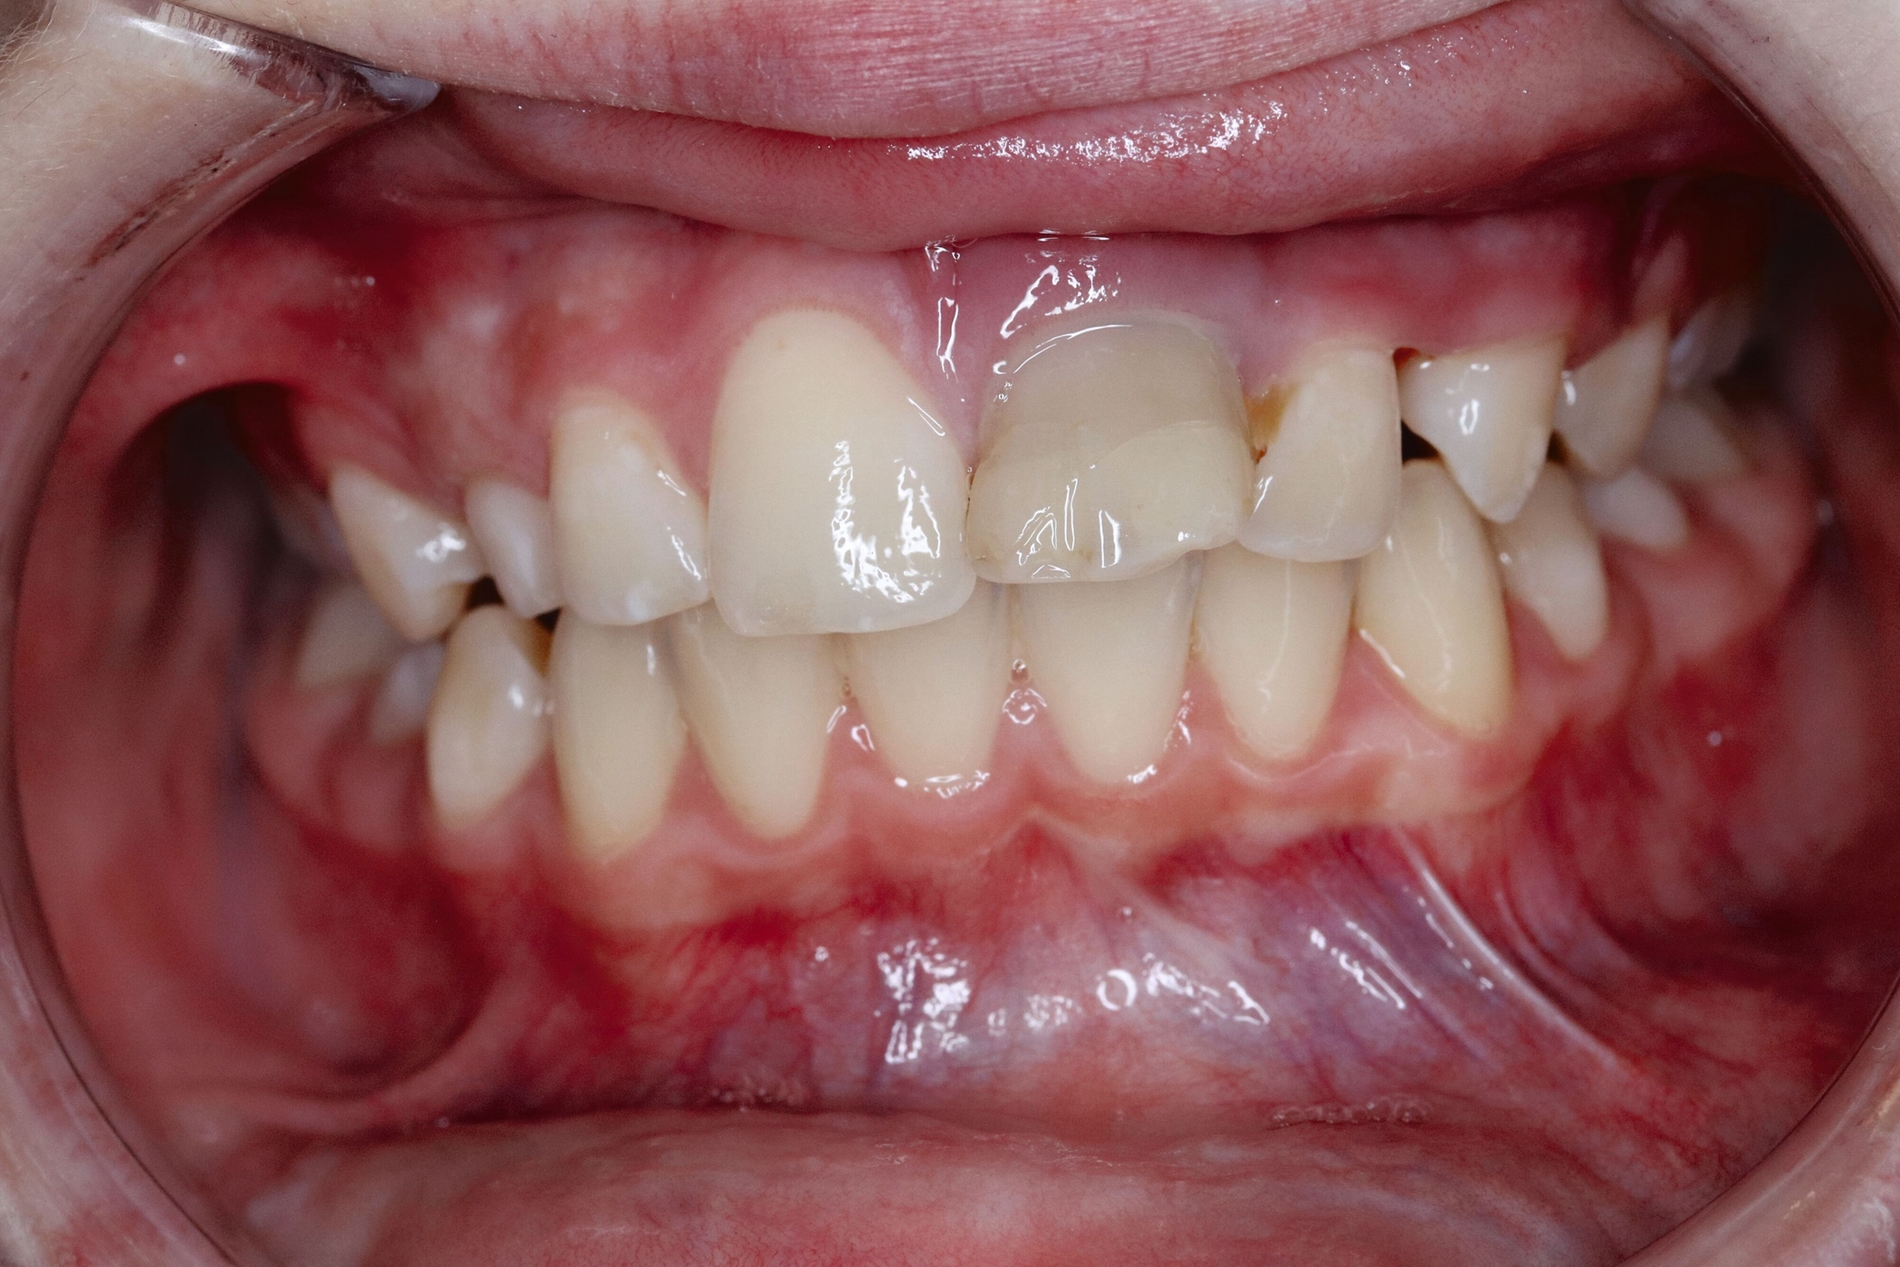

Der spätere kunststoffadhäsive Aufbau des Zahnes erfolgte nach Erreichen des isogingivalen Niveaus im Vergleich zum Nachbarzahn 11 durch kieferorthopädische Extrusion (Abbildung 5).

Ein Jahr später präsentiert sich das Transplantat in regio 21 reizfrei und perfekt in Okklusion stehend. Die Transplantation des verlagerten Eckzahns an die Stelle des Zahnes 21 war mit einer ausgezeichneten Wiederherstellung der knöchernen und weichgewebigen Situation verbunden (Abbildung 5).